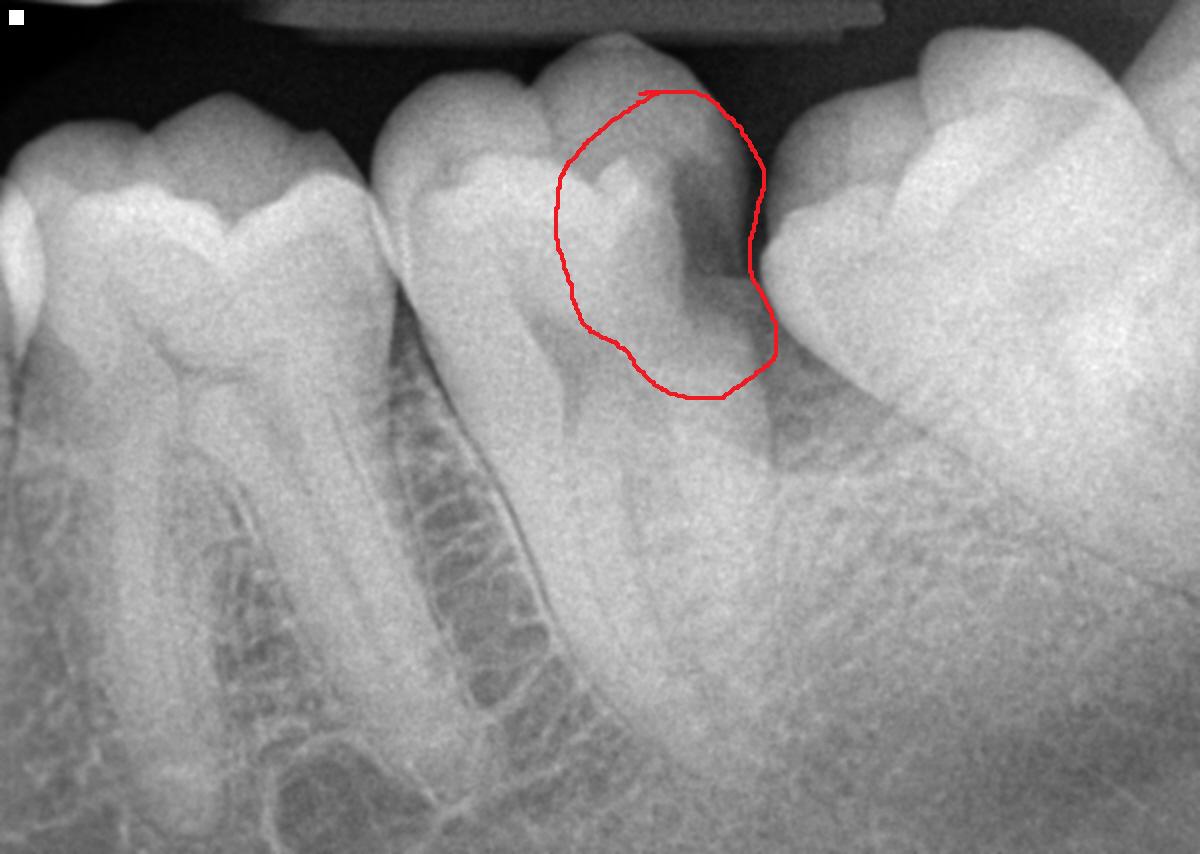

Obviously there is more scientific and dental verbage that can be used here, but that is the summary of what causes a cavity. Our mouths are dirty places and there are some nasty bugs in there. Some are known to cause cavities, others are known to cause gum and bone disease and some have been found to cause heart disease and/stroke (please refer to our previous blog entry about periodontal disease). The sugars and carbohydrates (chips, fries, bread, etc.) provide food for the bacteria and they also create a sticky matrix on the tooth that the bacteria can adhere. Most small cavities cause no symptoms. This is why you should see your dentist at least twice a year so we can detect these visually and radiographically. When you start noticing sweet or cold sensitivity, the cavitation is deeper in the tooth and the nerve is detecting those acids and temperature changes. The next step is the bacteria get so deep they enter the nerve chamber then it’s root canal time because the tooth hurts and the nerve within the root is now infected. So keep those preventative exam and hygiene appointments so we can catch those little cavities early. As you can see in the first x-ray, the dark area (aka the cavity) is shallow and the patient was having no symptoms. The second photo shows a cavity in the nerve and the patient said it was more painful than giving birth.